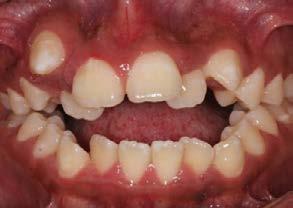

Se presenta una paciente clase ll esquelética en los estudios extrao rales en la fotografía de frente se ve hiperdivergente con una mordi da profunda de 5mm, un diastema, y refiere como motivo de consulta "no me gusta el espacio entre mis dien tes" (Figura 1).

En los estudios intraorales de inicio en las fotografías se muestra en la de frente el diastema anterior, con la línea media dental superior e inferior no coincidentes, la mordida profun da anterior (Figura 2), en la lateral derecha clase l molar y canina bila teral (Figura 3), el apiñamiento leve superior e inferior y la forma de las arcadas.